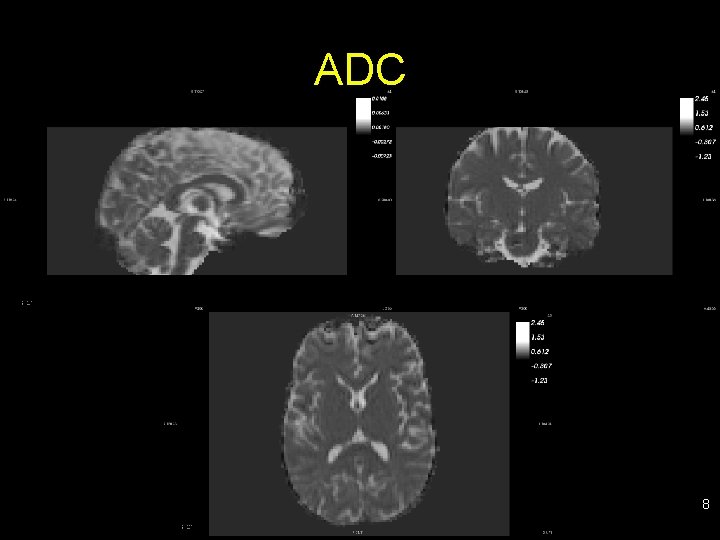

Examples of scalar maps • FA: fractional anisotropy (fiber density, axonal diameter, myelination in WM) • RA: relative anisotropy • VR: volume ratio • IVC: inter-voxel correlation (diffusion orientation agreement in neighbors) • ADC: apparent diffusion coefficient (magnitude of diffusion; low value organized tracts) • RD: radial diffusivity • AD: axial diffusivity • … 6

ADC 8